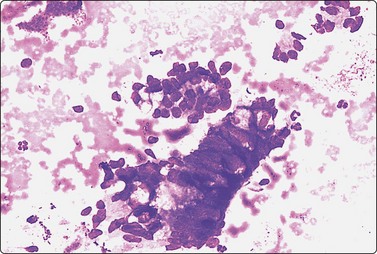

Yolk sac tumor (Figs 13.37 and 13.38)14,53-56,59-61,63

Most cytologic reports are based on FNA performed on metastatic sites. A detailed account of the morphologic spectrum of endodermal sinus tumor has been reported by Akhtar et al.53

image image

Fig. 13.37 Endodermal sinus tumor

(A) Polypoid epithelial fragment of large malignant cells with pale, almost clear, vacuolated cytoplasm (MGG, HP); (B) Corresponding tissue section (H&E, IP).

Fig. 13.38 Endodermal sinus tumor

(A) A glomeruloid cell cluster with vacuolated cytoplasm on a mucoid background (DQ, IP); (B) Cell cluster with a vascular stalk and several hyaline globules.

Criteria for diagnosis

Mucoid background,

Glomeruloid structures,

Schiller-Duval bodies (characteristic finding when present),

Very immature cells, prominent nucleolus, basophilic cytoplasm,

Small naked nuclei,

Intra- or extracellular PAS-positive hyaline globules (AFP positive),

Prominent cytoplasmic vacuoles and distinct cell boundaries confer a clear-cell appearance,

Immunocytochemistry: focal staining for AFP, AE1/AE3 and PLAP; negative for OCT image.

Pure yolk sac tumors are almost always encountered in infants and young children but rare in the first 6 months of life.49 In adults, this pattern is seen in approximately 40% of nonseminomatous GCT;12 however, it can easily be mistaken for embryonal carcinoma in FNA smears. This is why most reported cases are of metastatic tumors. Hyaline globules and eosinophilic membrane-like material are hints to the diagnosis of this tumor type (Fig. 13.38B). In infants and young children, the aforementioned cytological criteria permit a confident diagnosis by FNA.